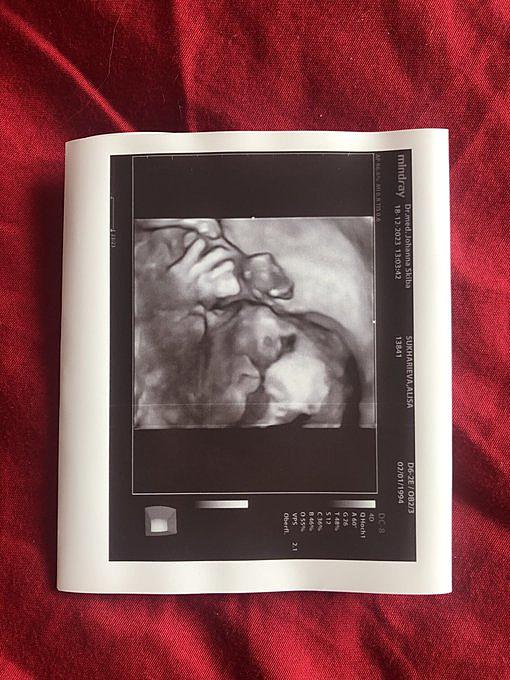

Причиной этого решения стало желание Сухарева больше времени проводить с семьёй. В ближайшем будущем он станет отцом, и для него важно не пропустить этот важный момент в жизни. Киберспортсмен признался, что CS всегда будет занимать особое место в его сердце, и поэтому он постарается найти время для трансляций своих игр на платформе Twitch. Вероятно, Сухарев больше не продолжит свою карьеру профессионального игрока.